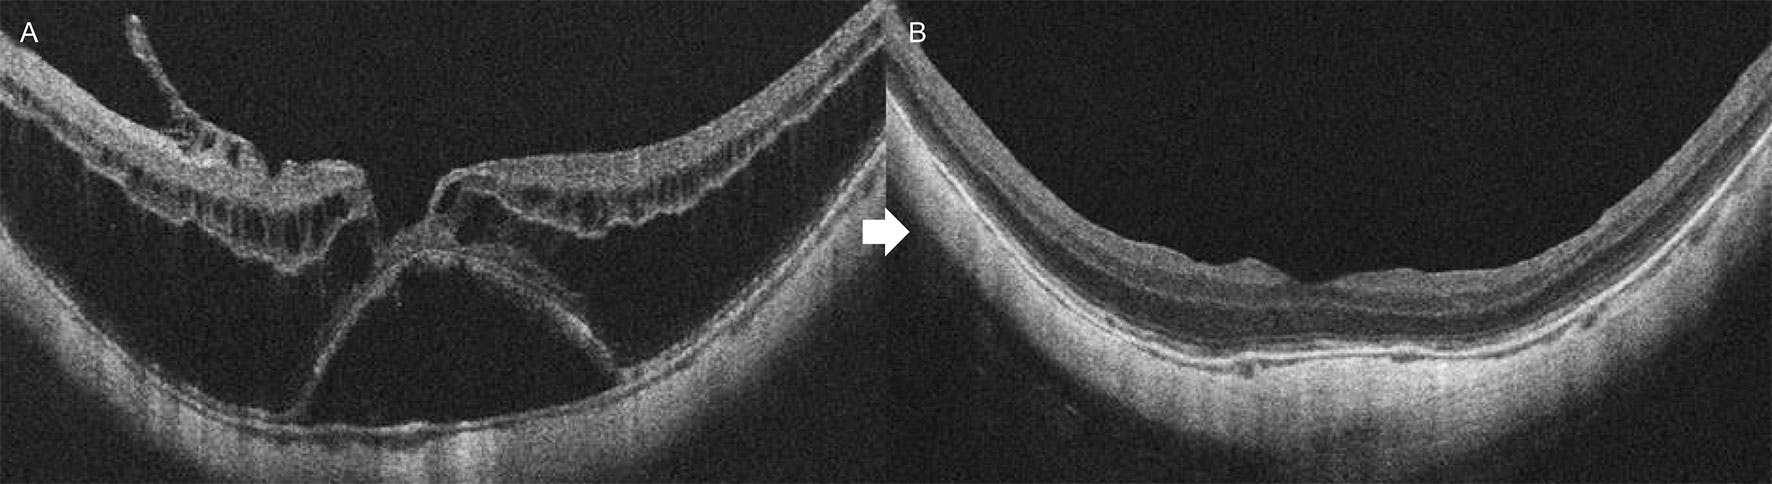

In eyes with a gradual MTM progression to foveal RD with worsening vision (Figure 1C and Figure 2), PPV is strongly recommended to prevent progression to FTMH and further vision loss.

Figure 2. This eye with MTM, foveal RD, and a very thin fovea (A) was treated with PPV, fovea-sparing ILM peeling, and no tamponade (B). VA improved from 20/80 to 20/50 with complete schisis resolution.